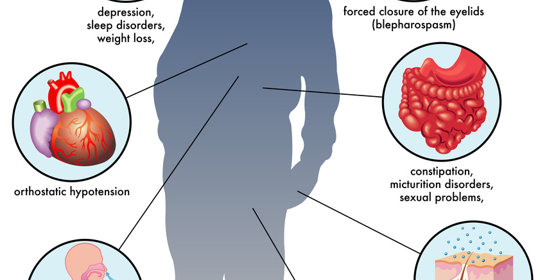

腦幹出血:後遺症、症狀及治療

腦幹出血:症狀、嚴重性與後遺症